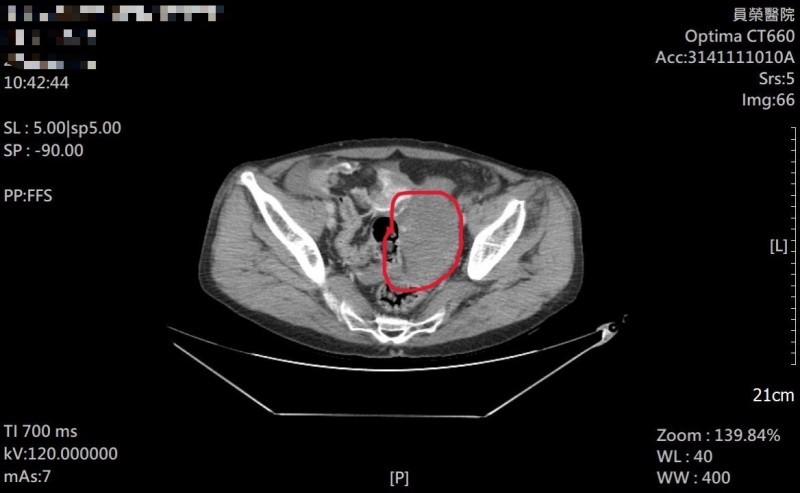

關鍵數字:一名年約 50 歲的男…